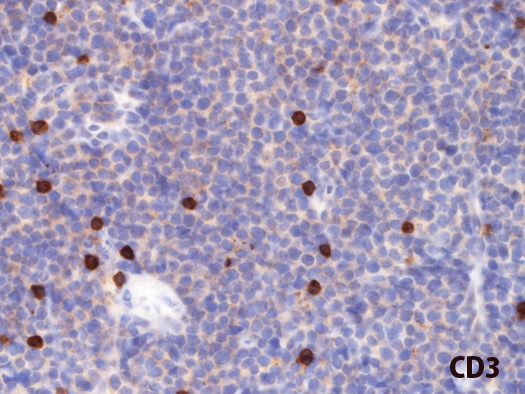

免疫染色とISH

kifCD3.jpg

CD20CD79aCD3CD10